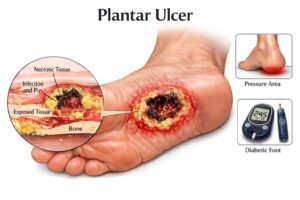

What Is a Plantar Ulcer? (And Why You Shouldn’t Ignore It) A plantar ulcer is an open wound or sore...